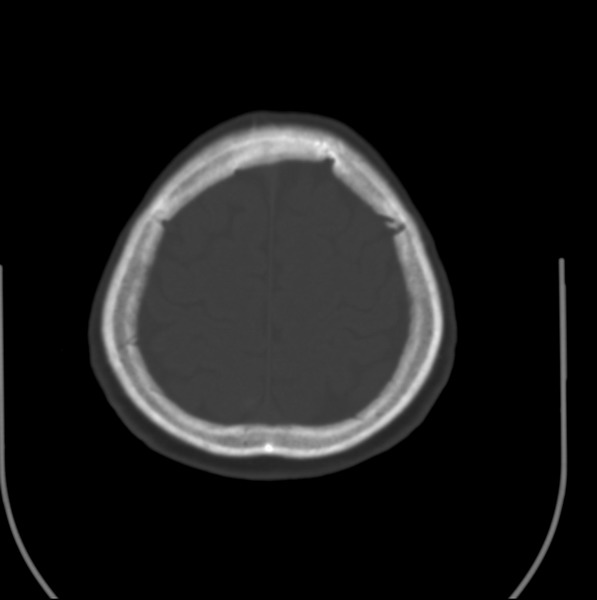

以下是引用余辉在2009-4-25 10:34:00的发言:[br]上矢状窦旁软组织肿块,内有钙化,与上矢状窦边界不清,灶后颅骨内板骨质增生硬化,支持考虑脑膜瘤,建议增强

以下是引用hmyj9在2009-4-25 14:21:00的发言:[br]病灶紧贴颅板处,中心高密度周围见软组织密度,局部颅板有增生,支持脑膜瘤诊断,建议增强。

以下是引用边生丽在2009-4-25 11:55:00的发言:[br][br] [br] 考虑脑膜瘤可能性大;建议行进一步检查。 [br] [br] [br]